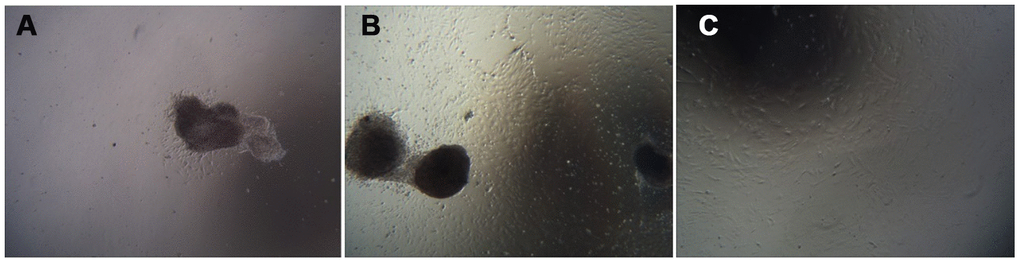

Cell growth morphology

The umbilical cord tissue pieces were inoculated in a 10 cm culture dish based on the characteristics of adherent mUCMSC growth. After 1 day, the cells were observed climbing out of the dish (Figure 4A). After 6 days, the cells isolated from the umbilical cord tissue expanded and spread within the surrounding space, and the confluence of the long spindle cells reached 80% (Figure 4B). Passaging was carried out, and the first purification sort was performed. After the P3 generation, the cells were homogeneous, long, fusiform and fibroblast-like (Figure 4C).

Figure 4. Cell growth morphology (100×). Note: (A) shows the first day of primary culture, as the cells migrate from the umbilical cord tissue. (B) shows the sixth day of primary culture, and the cells that grew were observed around the umbilical cord tissue. (C) is a cell from the P3 generation.